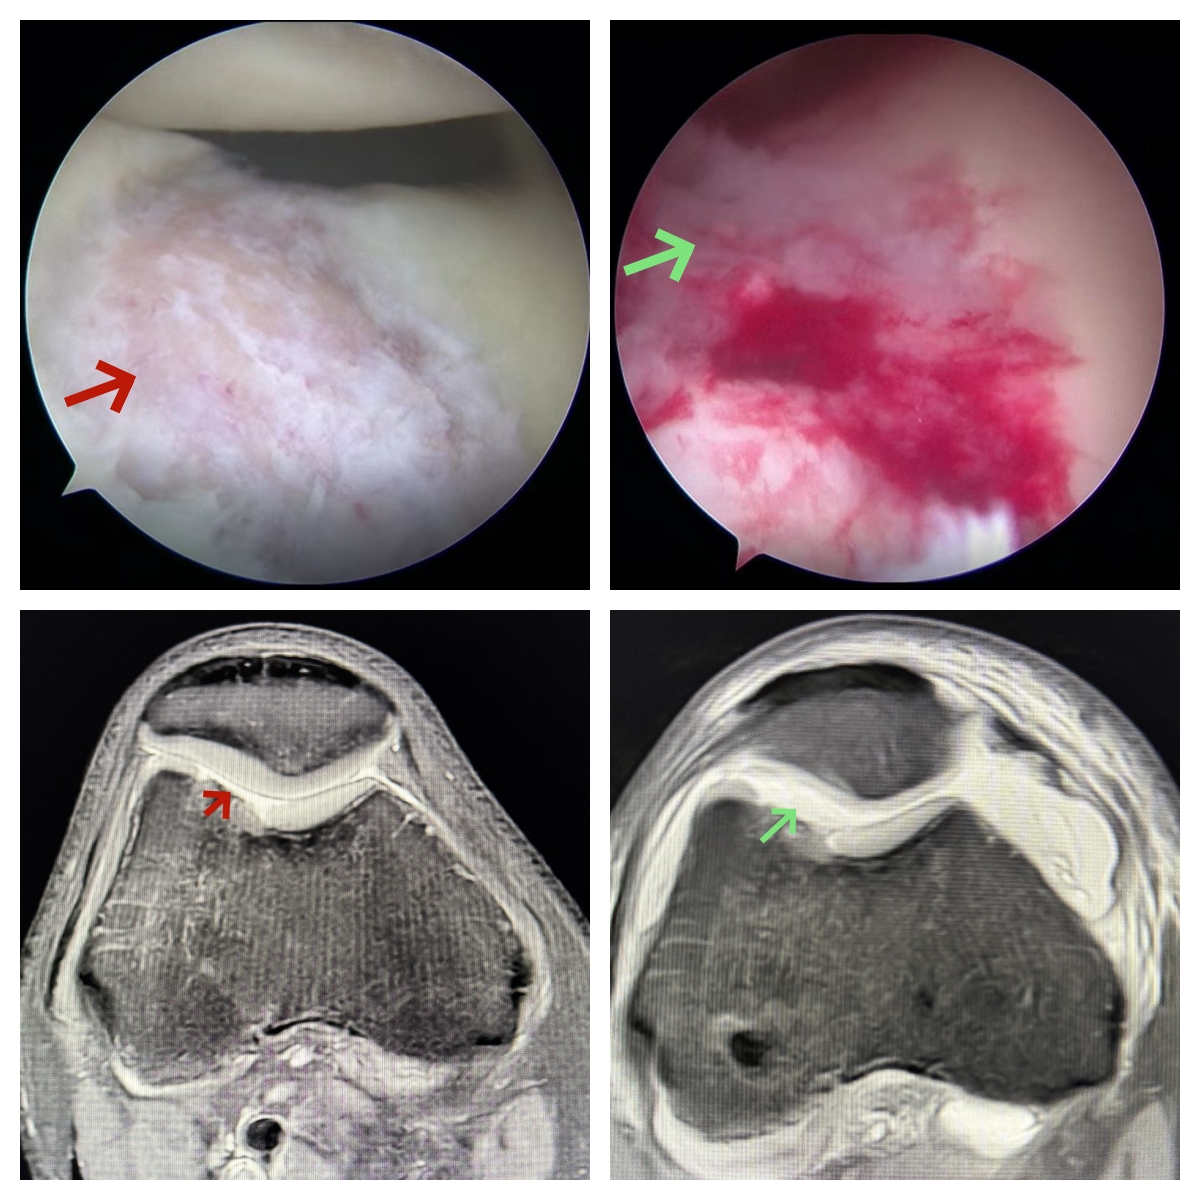

34岁的李某,于2024年9月下旬在打篮球过程中不慎扭伤右膝,进而出现疼痛、肿胀以及功能受限的状况。在家休养3个月后,肿胀虽有所减轻,但疼痛与运动功能障碍依旧存在,严重影响日常生活。为寻求进一步的诊断与治疗,患者于2025年1月来到中南大学湘雅三医院骨科运动医学门诊就医。根据患者病史、体格检查以及影像学表现,患者主要诊断为:1,右膝前交叉韧带断裂;2,右侧股骨滑车软骨Outerbridge IV°损伤(面积约2×4cm²)。

在与患者充分讨论治疗方案后,骨科何金深副主任医师、王梓力主治医师和梁驰总住院医师于2025年1月8日为患者施行了微创手术,即关节镜下右膝前交叉韧带重建+胶原蛋白诱导自体软骨成形术(Autologous Collagen Induced Chondrogenesis,ACIC)。一期为患者完成了软骨缺损修复,手术历时约1小时。术后复查磁共振成像(MR)表明手术效果确切,胶原蛋白软骨修复支架对软骨损伤实现了良好的覆盖。患者术后第二天就在医生指导下进行康复锻炼,恢复良好。目前已出院,且患者对疗效非常满意。